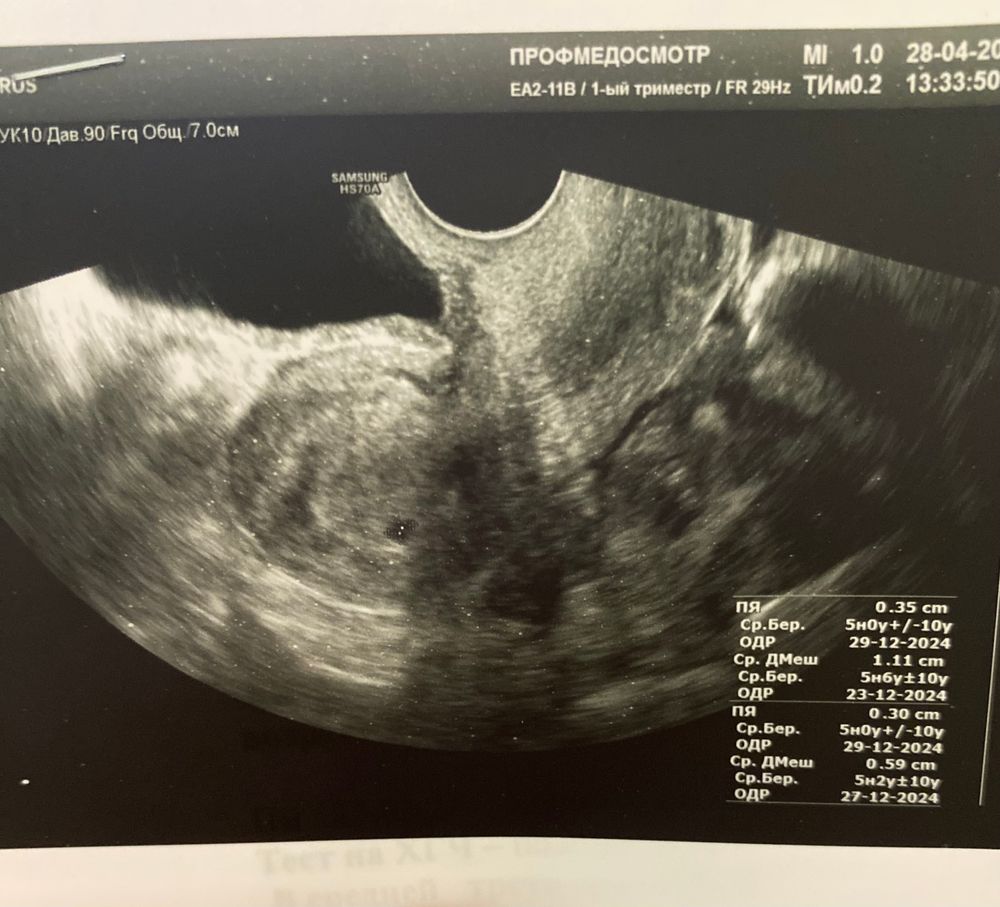

Самое главное, что нужно знать, это два плодных яйца. У одного ПДР на 23 декабря, у другого на 27.

Странно, что замеры двух ПЯ, а на снимке одно и без ЖМ. Наверно нижнее описание толи от предыдущего пациента, толи образец идеальной Б на этот срок 🤷‍♀️

Виктория, ПЯ 0,35 см, в заключении срок вообще не написан, просто маточная беременность малого срока

Елена Ксензова, а, ну по верхнему описанию, значит это ваше. Неопытная что ль какая то, ставит 5 нед +/- 10 у. Что такое У? 🤔🤭🤭🤭В общем, всё хорошо)